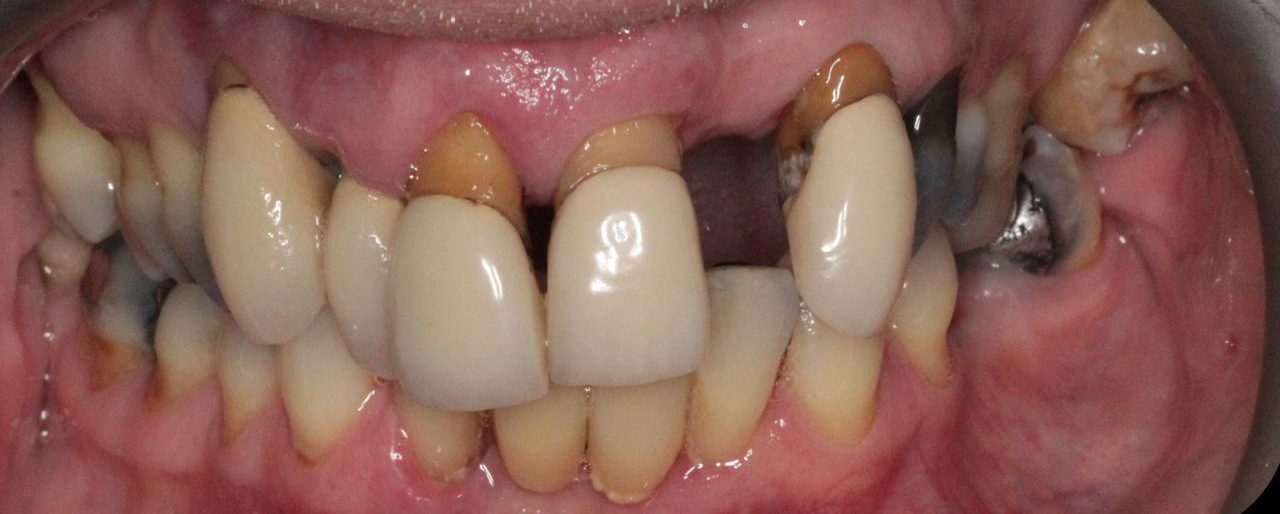

The patient presented to me with a failing upper dentition. Several anterior teeth were loose, and some posterior teeth were affected by mild periodontal disease. She was extremely conscious about her smile and had avoided seeing a dentist for years due to embarrassment about the condition of her teeth. Previously, she had seen a general dentist who could not offer her a solution that met her goals—she was adamant that she did not want to wear a removable denture that might impact her chewing and comfort.

After a thorough clinical assessment and careful discussion of her concerns and treatment objectives, it became clear that many of the upper teeth had a very poor prognosis and could not be saved long-term. We discussed several treatment options, and the patient decided to proceed with dental implants and an immediate fixed bridge, as she wanted a permanent solution that would allow her to regain her confidence and function.

Extractions and Immediate Implants (“Teeth-in-a-Day”)

On the day of surgery, we carefully removed the failing upper teeth, placed multiple dental implants, and immediately provided a fixed provisional bridge. This “teeth-in-a-day” approach meant the patient left with a full set of stable, fixed teeth the same day, avoiding any period without teeth or the need for a removable denture.